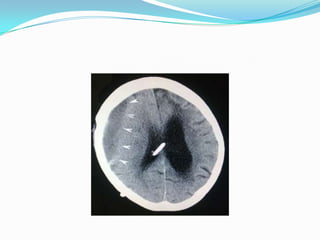

 CT brain demonstrated enlarged ventricles and

hypodensity of the white matter.